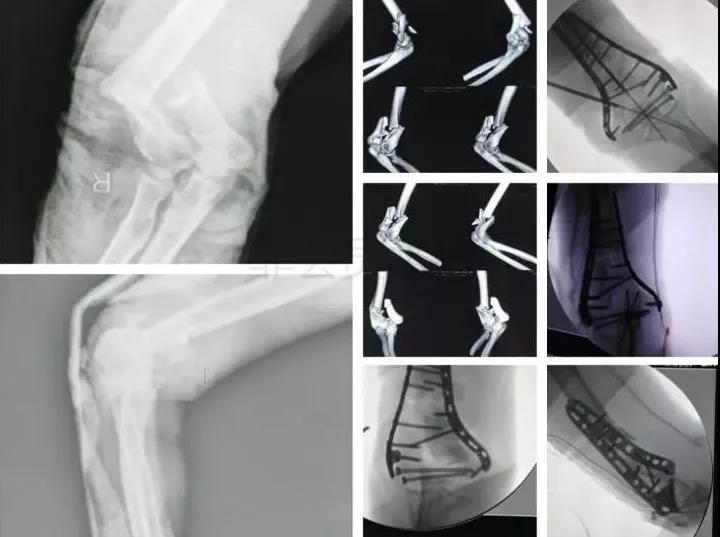

3)肱骨远端骨折

- 骨筋膜室综合征,立即减压。

- 前臂三大神经,肘血管损伤均可以探查。

4)复杂肘关节骨折(尺骨鹰嘴,桡骨头)

- 伤后1周内手术

- 2周后手术-骨化性肌炎

- 术后尽量不要肘关节制动,制动不超过2周。